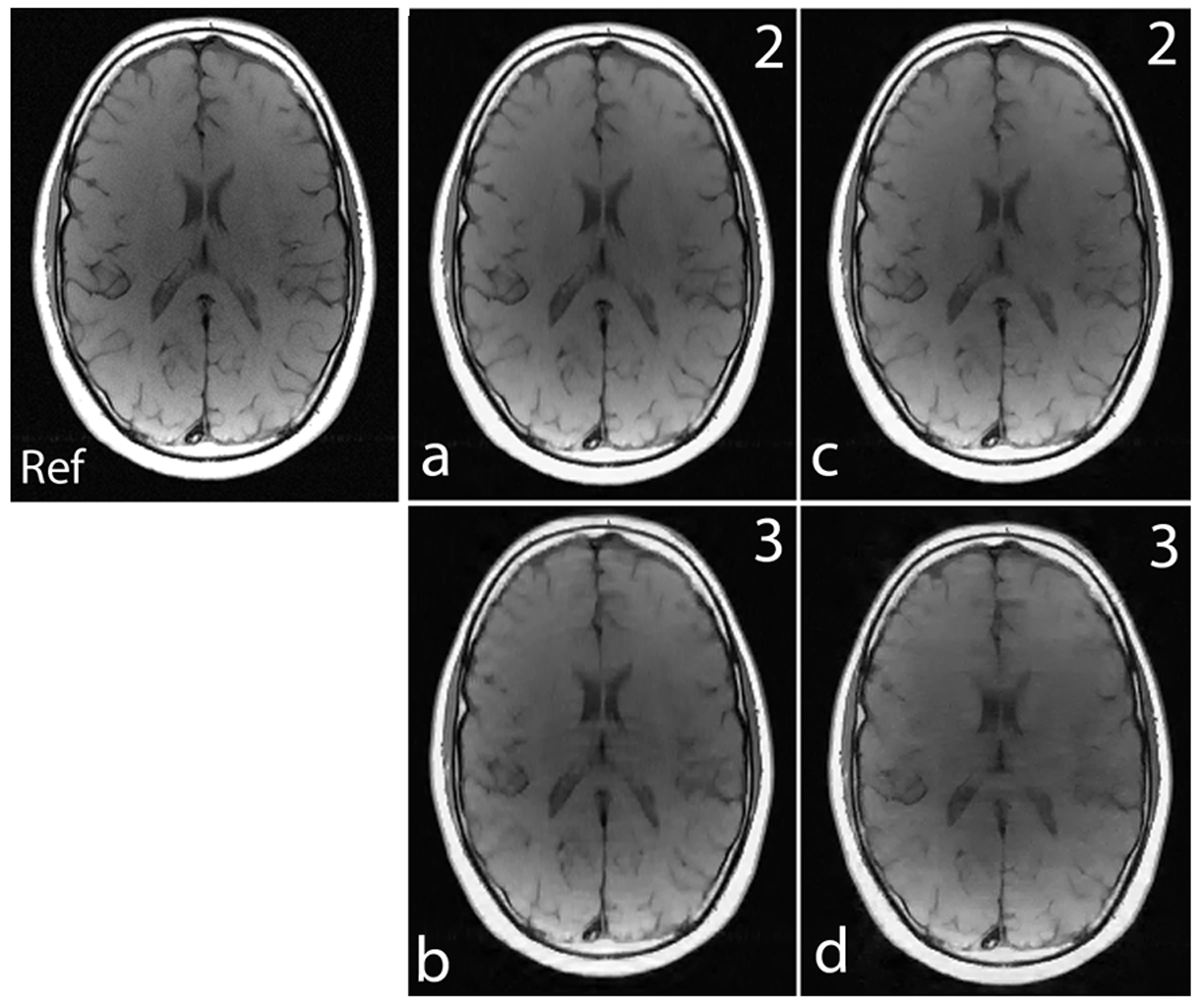

Fig. 5 show the images reconstructed with Fourier encoding and noiselet encoding using variable density random under-sampling and completely random under-sampling pattern respectively. The noiselet encoded CS-MRI performs similar to that of the Fourier encoded CS-MRI. This is due to the fact that in the case of variable density random under-sampling, the Fourier encoding judiciously exploits extra information about the data, namely the structure of k-space. The center of the k-space data has maximum energy and hence, by densely sampling the center of k-space, the Fourier encoding captures most of the signal energy and results in better performance.

First we investigated the effect of the number of channels on the reconstruction quality using the MCS framework. For a fixed number of measurements, the number of channels was varied and the mean of the relative error for 1000 such simulations was calculated. Fig. 6 shows the plot of the mean relative error versus the number of channels for the acceleration factors of 2 and 3. When the number of channels was two, the noiselet encoding scheme outperformed the Fourier encoding scheme for both the acceleration factors of 2 and 3. However, when number of channels was equal to one, the noiselet encoding outperformed the Fourier encoding for an acceleration factor of 2, but not for an acceleration factor of 3. It is interesting to note that noiselet encoding outperformed Fourier encoding for both acceleration factors when the number of channels was greater than one. These simulations suggest that noiselet encoding should take into account the sensitivity information while performing CS, and therefore noiselet encoding is potentially a better encoding scheme for MCS-MRI. Based on the fact that noiselet encoding performs better than Fourier encoding for multi-channel data, we investigated the performance of both the encoding schemes using muti-channel data.